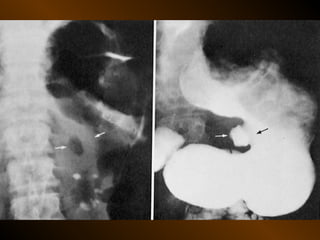

CĂNG GIÃN ỐNG TIÊU HÓA

• Căng giãn dạ dày

• Căng giãn tá tràng

• Căng giãn ruột non

• Căng giãn đại tràng

• Căng giãn ruột non lẫn đại tràng

• Nguyên nhân

• Cơ học : loét, ung thư, xoắn, bezoar

hẹp miệng nối, lồng ruột

• Không cơ học : toan máu, ure máu cao

• cắt tk X

• heroin

• viêm nhiễm lân cận: viêm tụy cấp, viêm túi mật cấp

• viêm tá tràng

• bệnh xơ cứng bì

• luput ban đỏ

• X quang: kết hợp giãn dạ dày trong tắc cao

ở ruột non